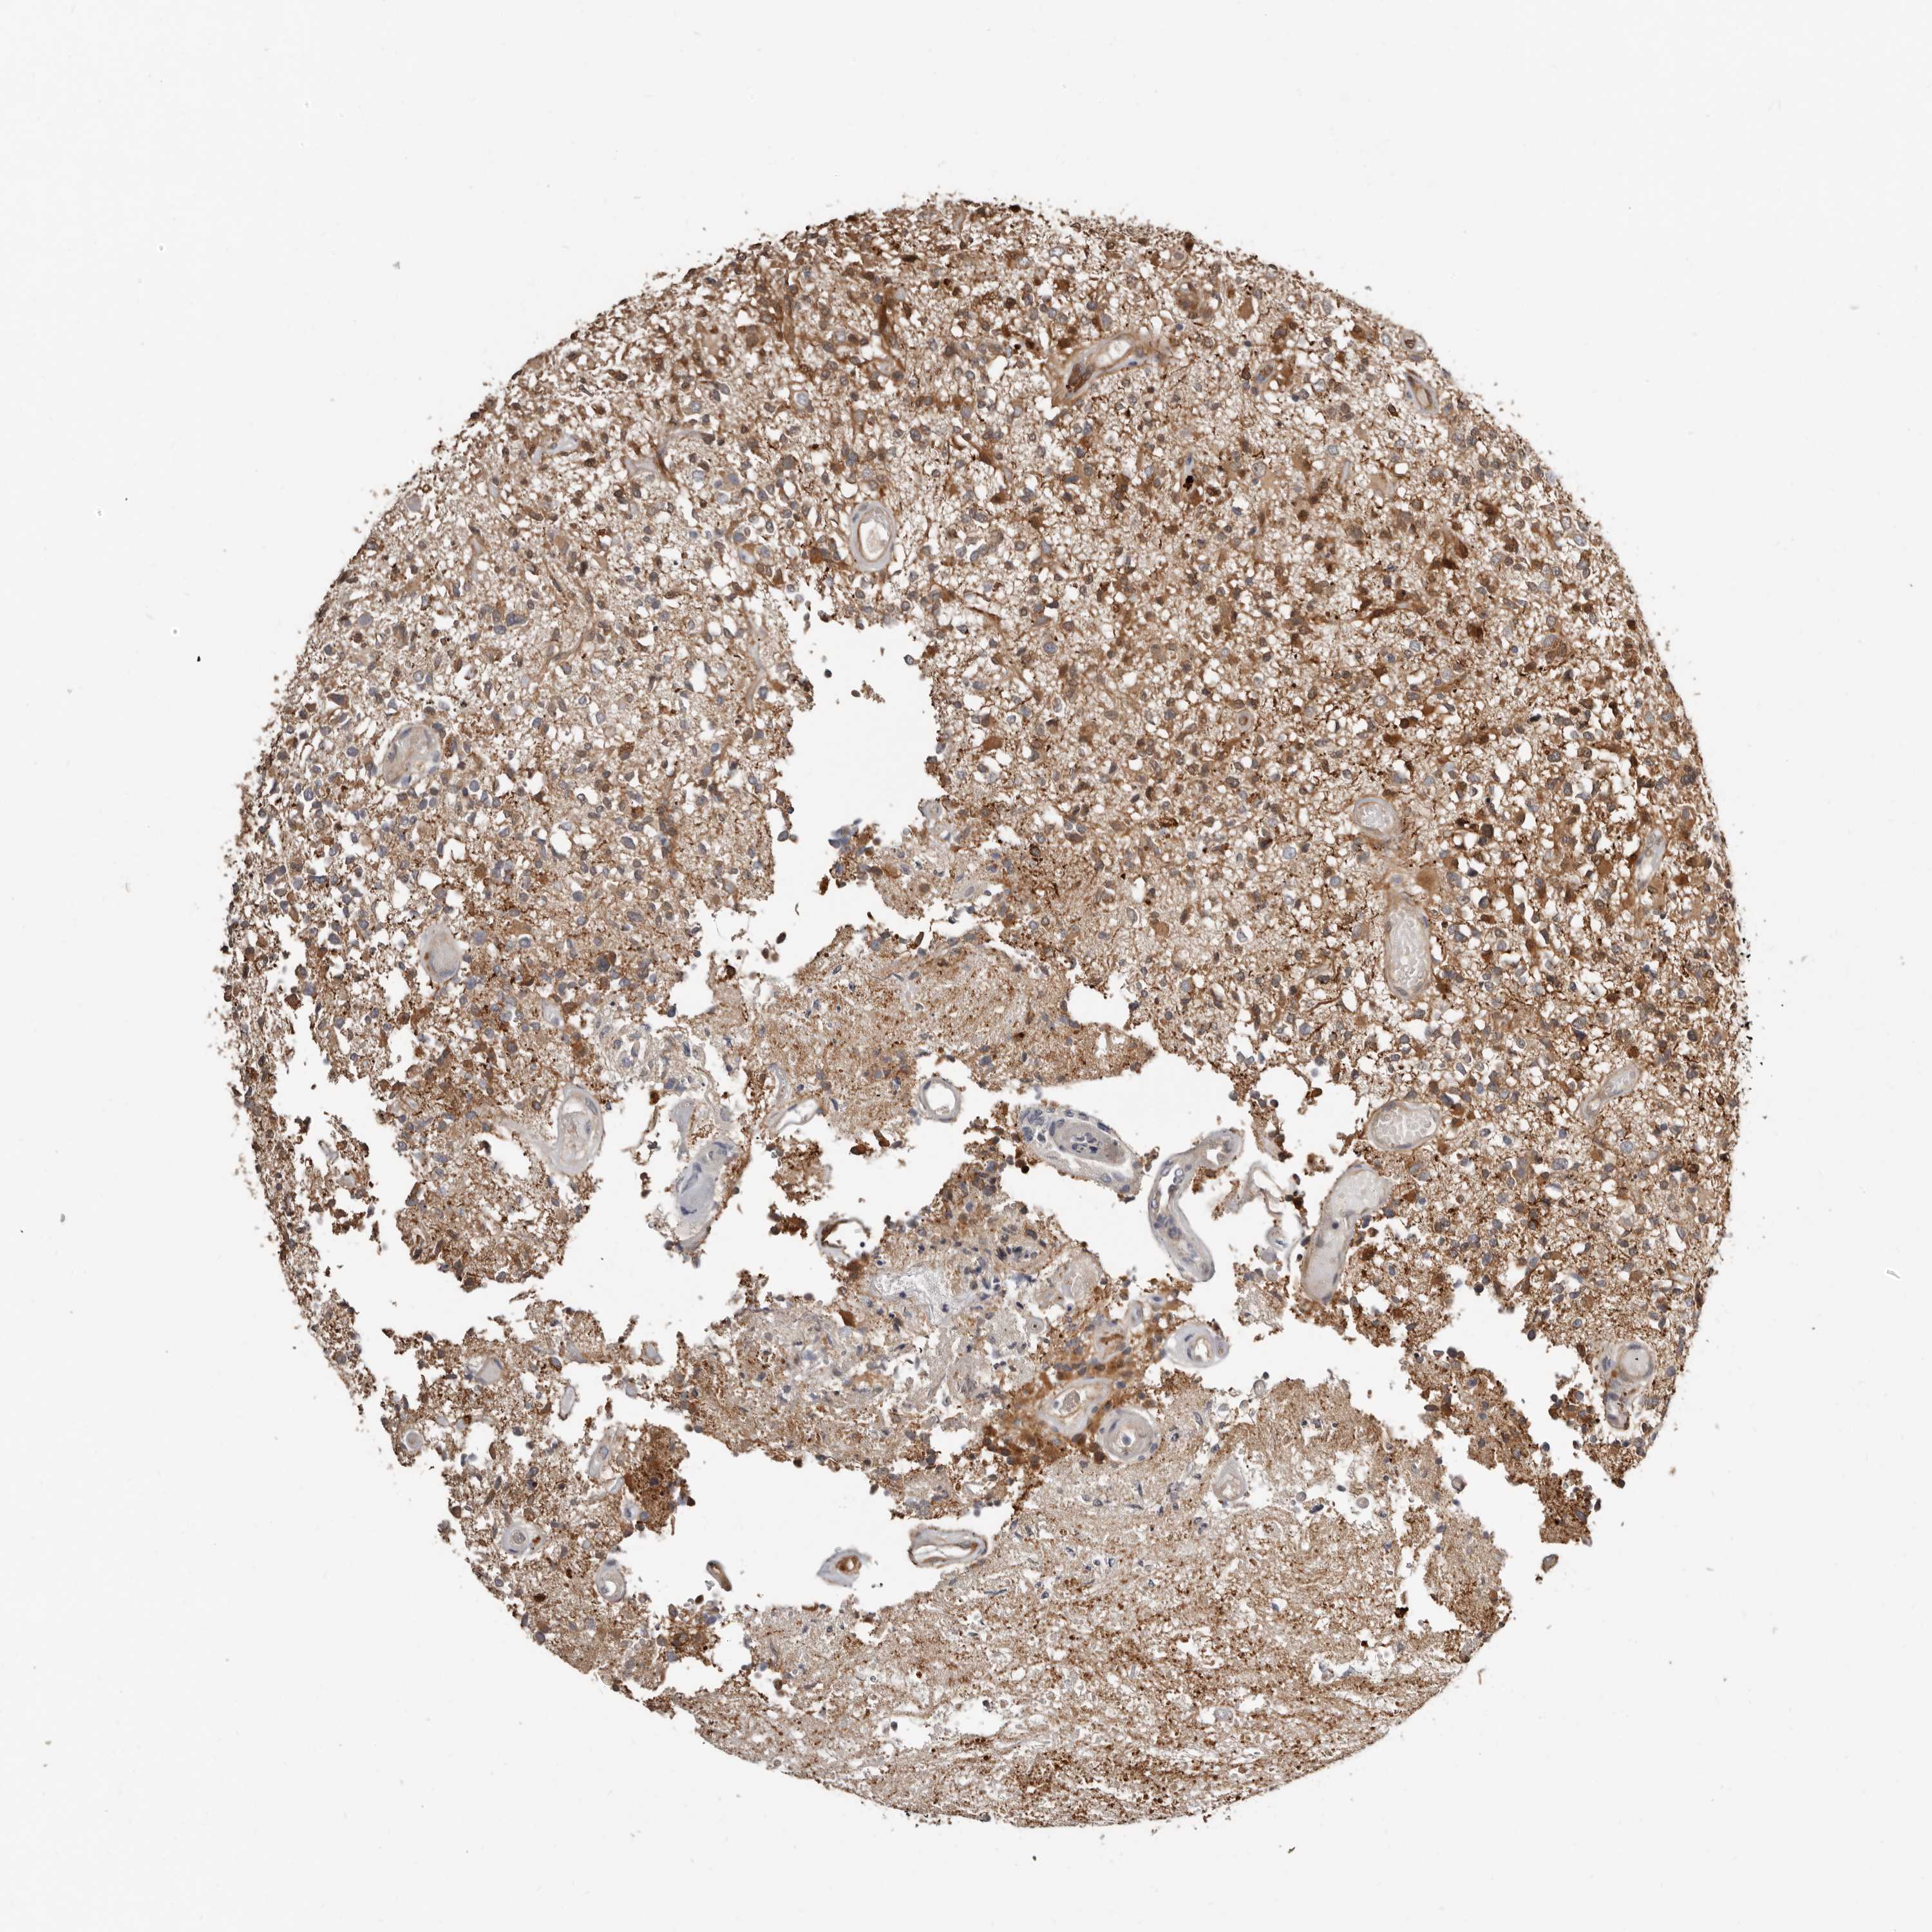

GLIOMA - Protein expressioni

A mouse-over function shows sample information and annotation data. Click on an image to view it in a full screen mode. Samples can be filtered based on level of antibody staining by selecting one or several of the following categories: high, medium, low and not detected. The assay and annotation is described here.

Note that samples used for immunohistochemistry by the Human Protein Atlas do not correspond to samples in the TCGA dataset.

Antibody stainingi

Antibody staining in the annotated cell types in the current human tissue is reported as not detected, low, medium, or high, based on conventional immunohistochemistry profiling in selected tissues. This score is based on the combination of the staining intensity and fraction of stained cells.

Each image is clickable and will lead to virtual microscopy that enables deeper exploration of all samples and also displays staining intensity scores, fraction scores and subcellular localization as well as patient and tissue information for each sample.

Antibody HPA028891

Staining

High

Medium

Low

Not detected

Intensity

Strong

Moderate

Weak

Negative

Quantity

>75%

75%-25%

<25%

None

Location

Nuclear

Cytoplasmic/membranous

Cytoplasmic/membranous,nuclear

Glioma, malignant, High grade

Glioma, malignant, Low grade

Glioblastoma, NOS